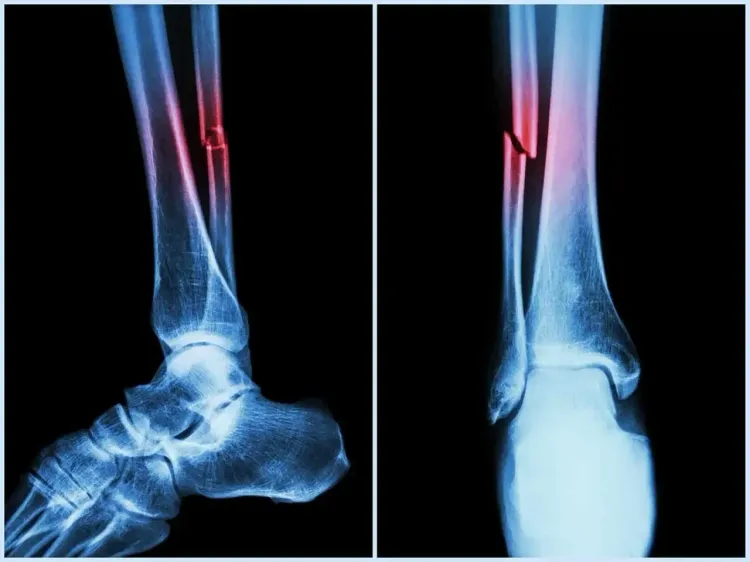

The automated technology evaluates vertebral fracture assessment (VFA) images to identify abdominal aortic calcification (AAC), which is a crucial indicator associated with heart attacks, strokes, and falls.

Additional research by Marc Sim of ECU revealed that AAC is not only a marker for cardiovascular risk but also a potent predictor of falls and fractures. In fact, AAC has shown to be more predictive than conventional fall risk factors such as bone mineral density and prior fall history.

"The greater the degree of calcification in your arteries, the higher your risk of falls and fractures," Sim noted, emphasizing that clinicians usually neglect vascular health in fall risk assessments, an oversight this algorithm addresses.